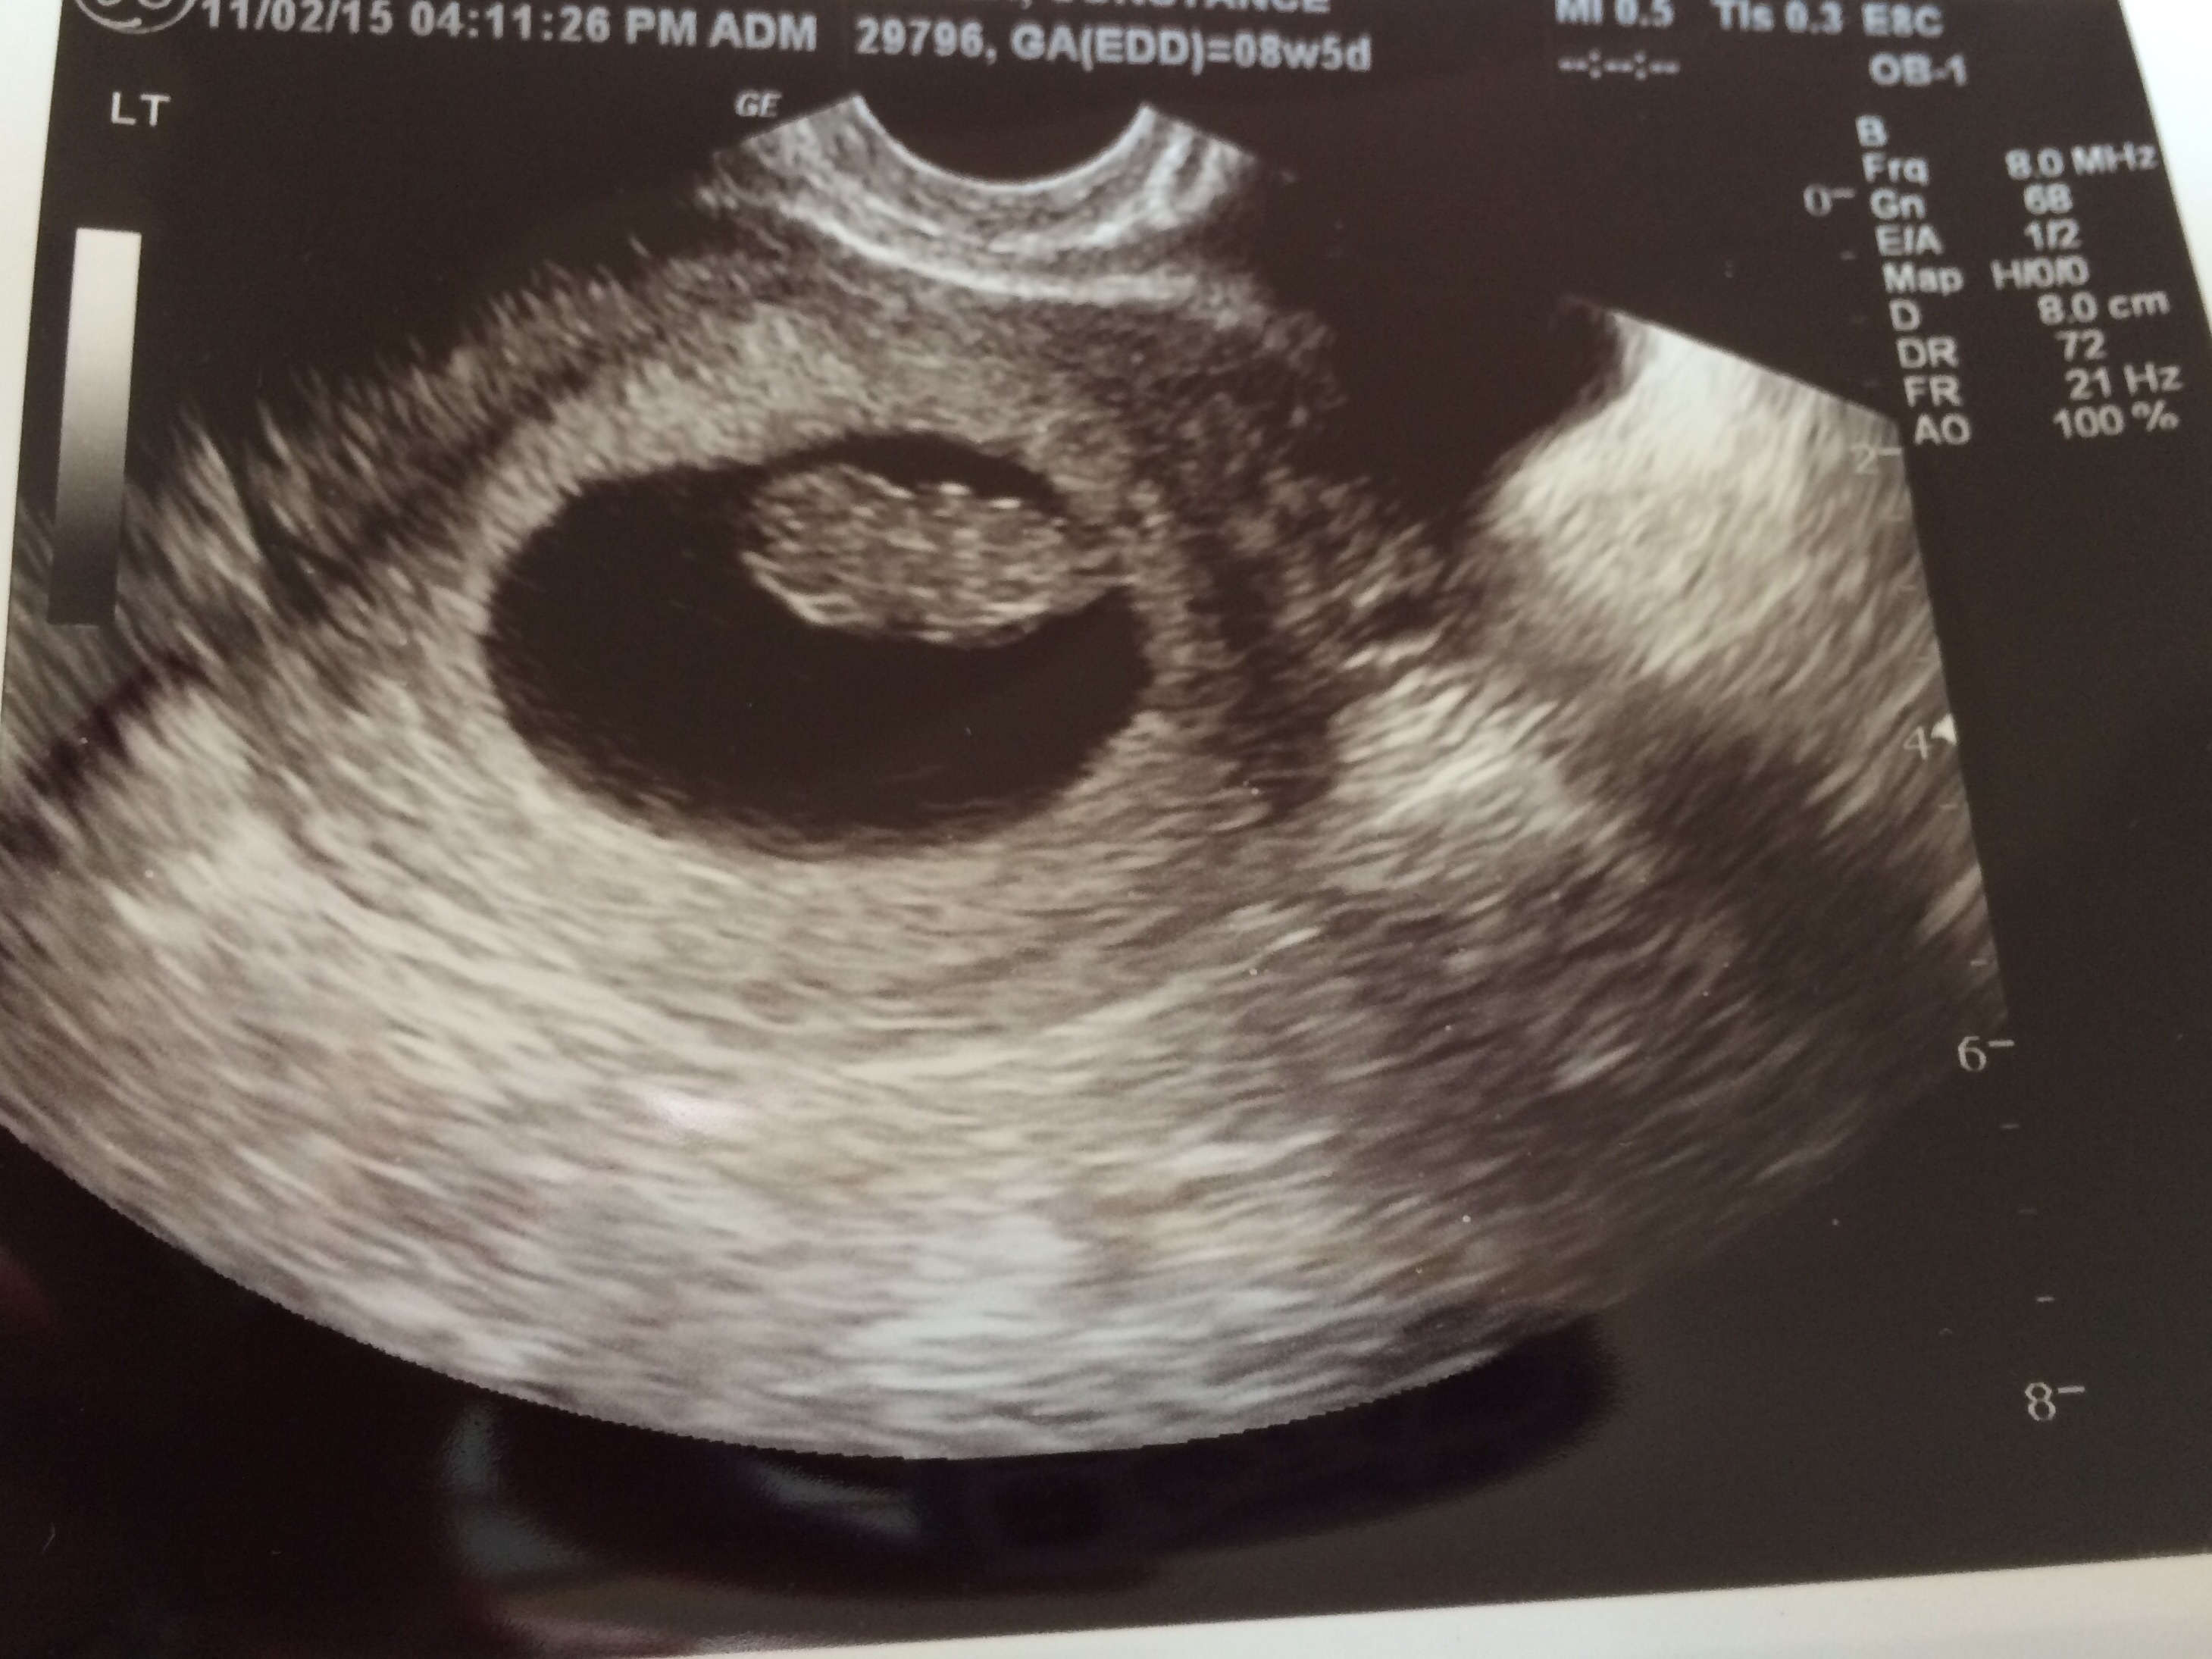

Went in for first official u/s today. 8 weeks 5 days based on LMP. Finally got to see our precious baby and the heartbeat. My OB also pulled out the Doppler and we got to hear it too!! 175 bpm and measuring 9 weeks!! I feel so much better after finally seeing Bean!